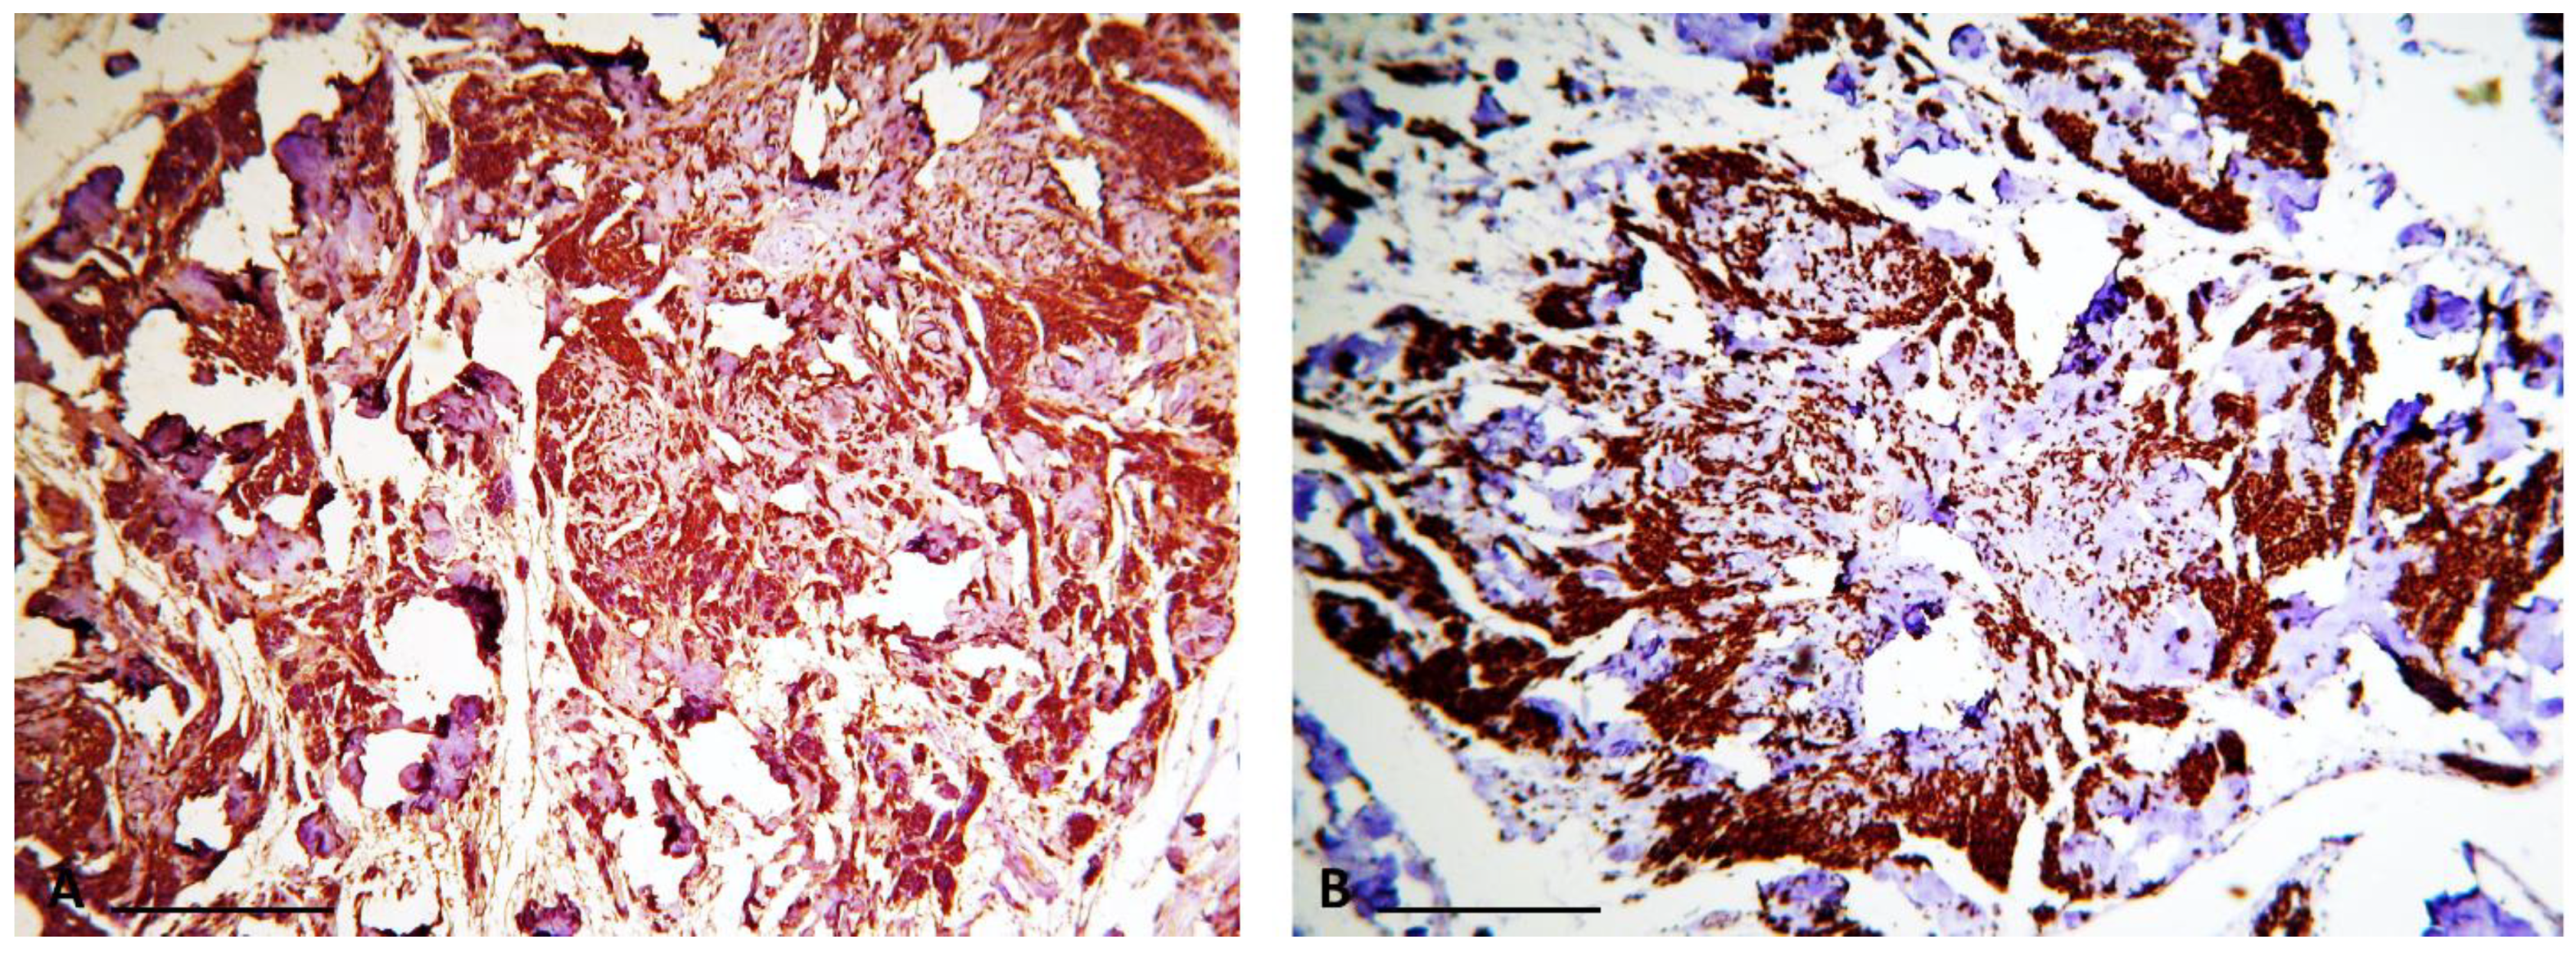

Masson’s trichrome staining confirmed that the central core of the rosettes was composed of collagen fibers. Subsequent immunohistochemical study revealed diffuse expression of S100 protein (as the most commonly used marker to detect tumoral cells) [6] in the tumoral cells, confirming the Schwann cell origin of the tumor (Figure 1 and Figure 2). Additionally, staining for the neural markers showed focal positive expression for Neuron Specific Enolase (NSE) and negative for synaptophysin which confirmed our diagnosis (Figure 3 and Figure 4).

Microscopically, neuroblastoma-like schwannoma can mimic other small round cell tumors, as originally described by Goldblum JR et al., and the presence of these small round cells along with rosette formation may cause confusion with primitive neuroectodermal tumors (PNETs) and neuroblastoma. Zachary T. Lewis believes that the name “neuroblastoma-like schwannoma” may overestimate these similarities [13]. Neuroblastoma-like schwannoma can be differentiated from mentioned entities based on the presence of areas of conventional schwannoma, encapsulation, lack of mitoses and atypia, along with diffuse positivity for S100 protein [2].

Immunohistochemical methods helped us to reach a definite diagnosis. Indeed, in our case, the tumor cells were strongly and diffusely positive for S100 protein and focally positive for NSE. Neuroblastoma-like schwannoma showed focal areas with typical immunophenotyping of conventional schwannoma and all tumor cells were strongly and diffusely positive for S100 protein, but typically negative for other markers of neural differentiation, such as synaptophysin [3]. However, there are reports in which the tumor cells show positivity for other neural markers such as NSE [9].

Figure 3. Immunohistochemical profile of neuroblastoma-like schwannoma (10× objective lens): (A) Schwann cells show strong and diffuse positivity for S100 marker; (B) Tumor cells are focally stained by Neuron Specific Enolase (scale bar = 100 μm).